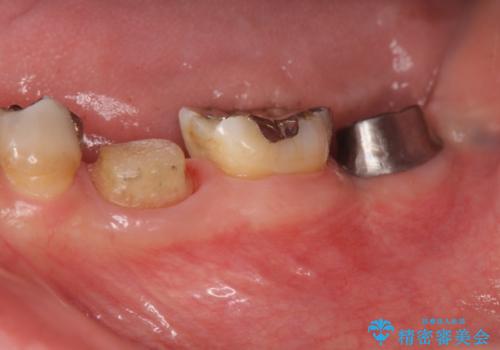

- 左下奥歯の咬合時疼痛を訴えて来院されました。

最後方臼歯周囲には大きな透過像が見られ、破折が強く疑われること抜歯が想定されることを理解していただき銀歯を除去したところ破折が認められたため抜歯を行いました。

今後の機能回復方法としてインプラント治療を希望されたため、将来的に大規模な骨造成が必要とならないよう歯槽堤保存術を抜歯と同時に行いました。